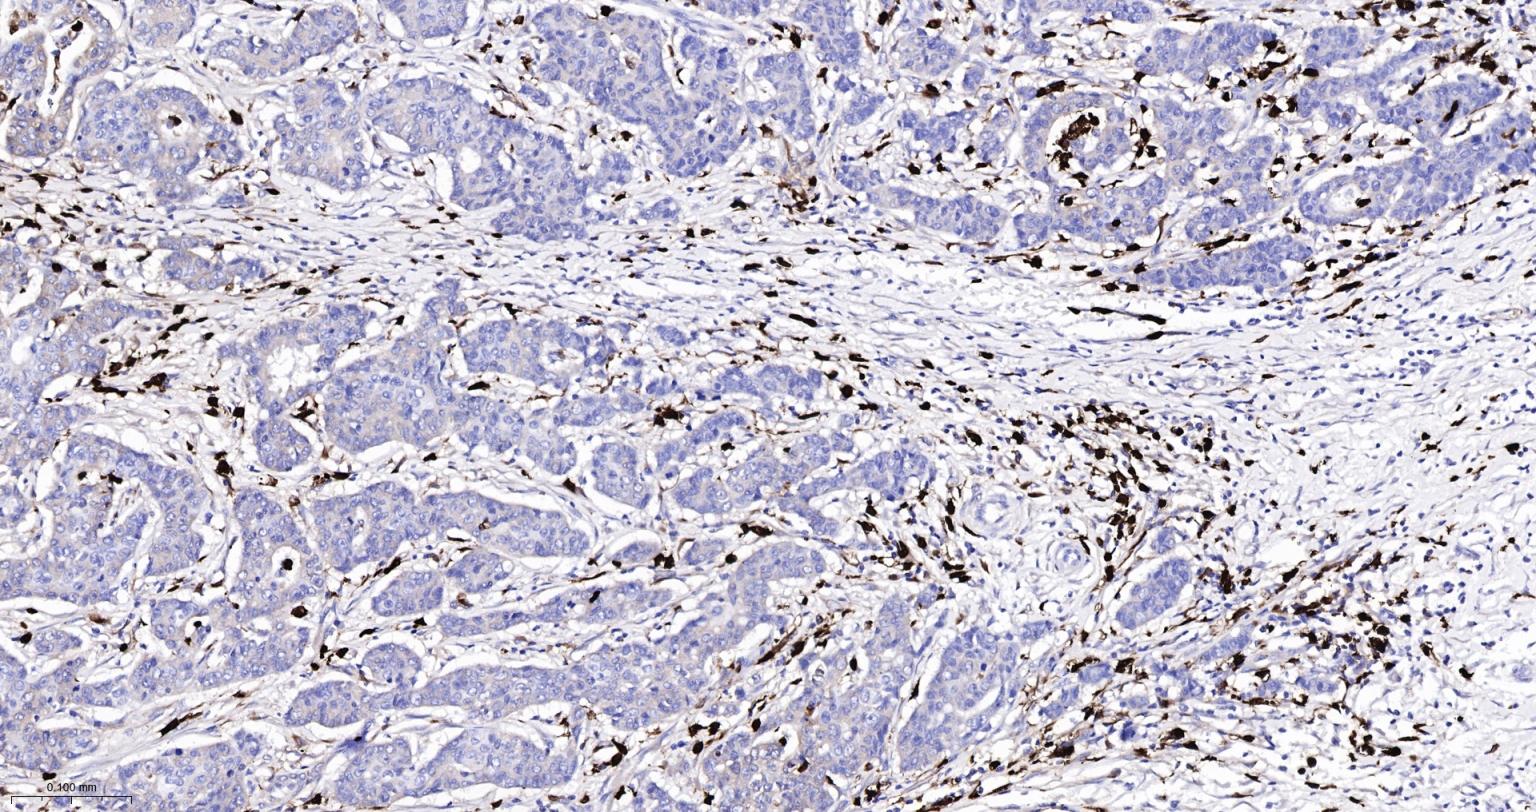

Paraformaldehyde-fixed, paraffin embedded Human Lung Cancer; Antigen retrieval by boiling in sodium citrate buffer (pH6.0) for 15 min; Antibody incubation with S100A8 Monoclonal Antibody, Unconjugated(bsm-61167R) at 1:200 overnight at 4°C, followed by conjugation to the SP Kit (Rabbit, SP-0023)and DAB (C-0010) staining.